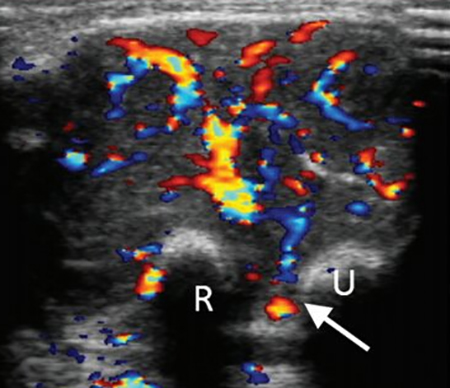

软组织肉瘤最初的症状是无痛性的肿块,没有什么特异性的症状。软组织肉瘤好发生于头颈部、泌尿生殖器官以及躯干四肢。其中躯干四肢、头颈部比较表浅容易发现。家长在给孩子洗澡、换衣服的时候可以摸到质地较硬的肿块,如果这些肿块在短时间内快速的生长,就要引起注意了,家长需要带孩子到专业肿瘤医院详细检查一下。